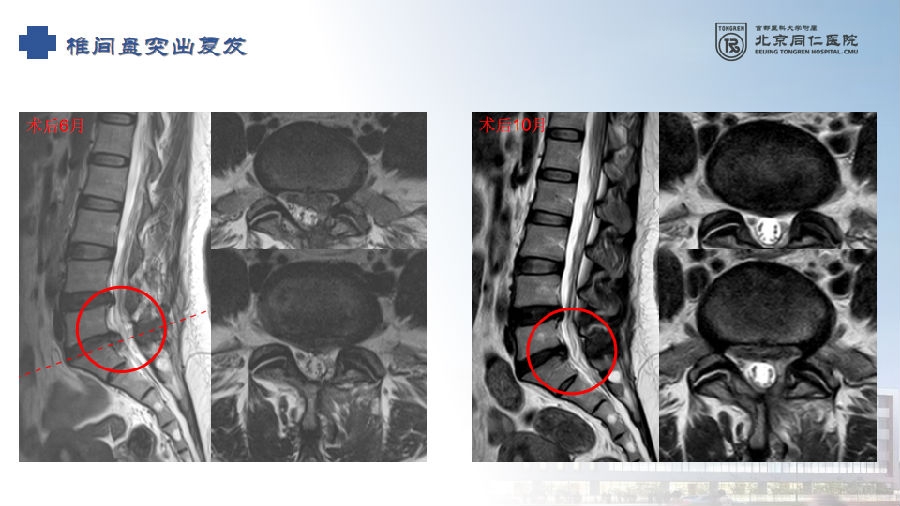

六、复发(2.27%)

病例(椎间盘突出复发)

女,42岁。

主诉:腰痛伴左下肢疼痛2月。

查体:疼痛放射至左侧臀部、大腿后侧、小腿后外侧。

思考和建议

完整切除突出的椎间盘

切除的椎间盘为影像学体积150%

视情况缝合纤维环,避免复发